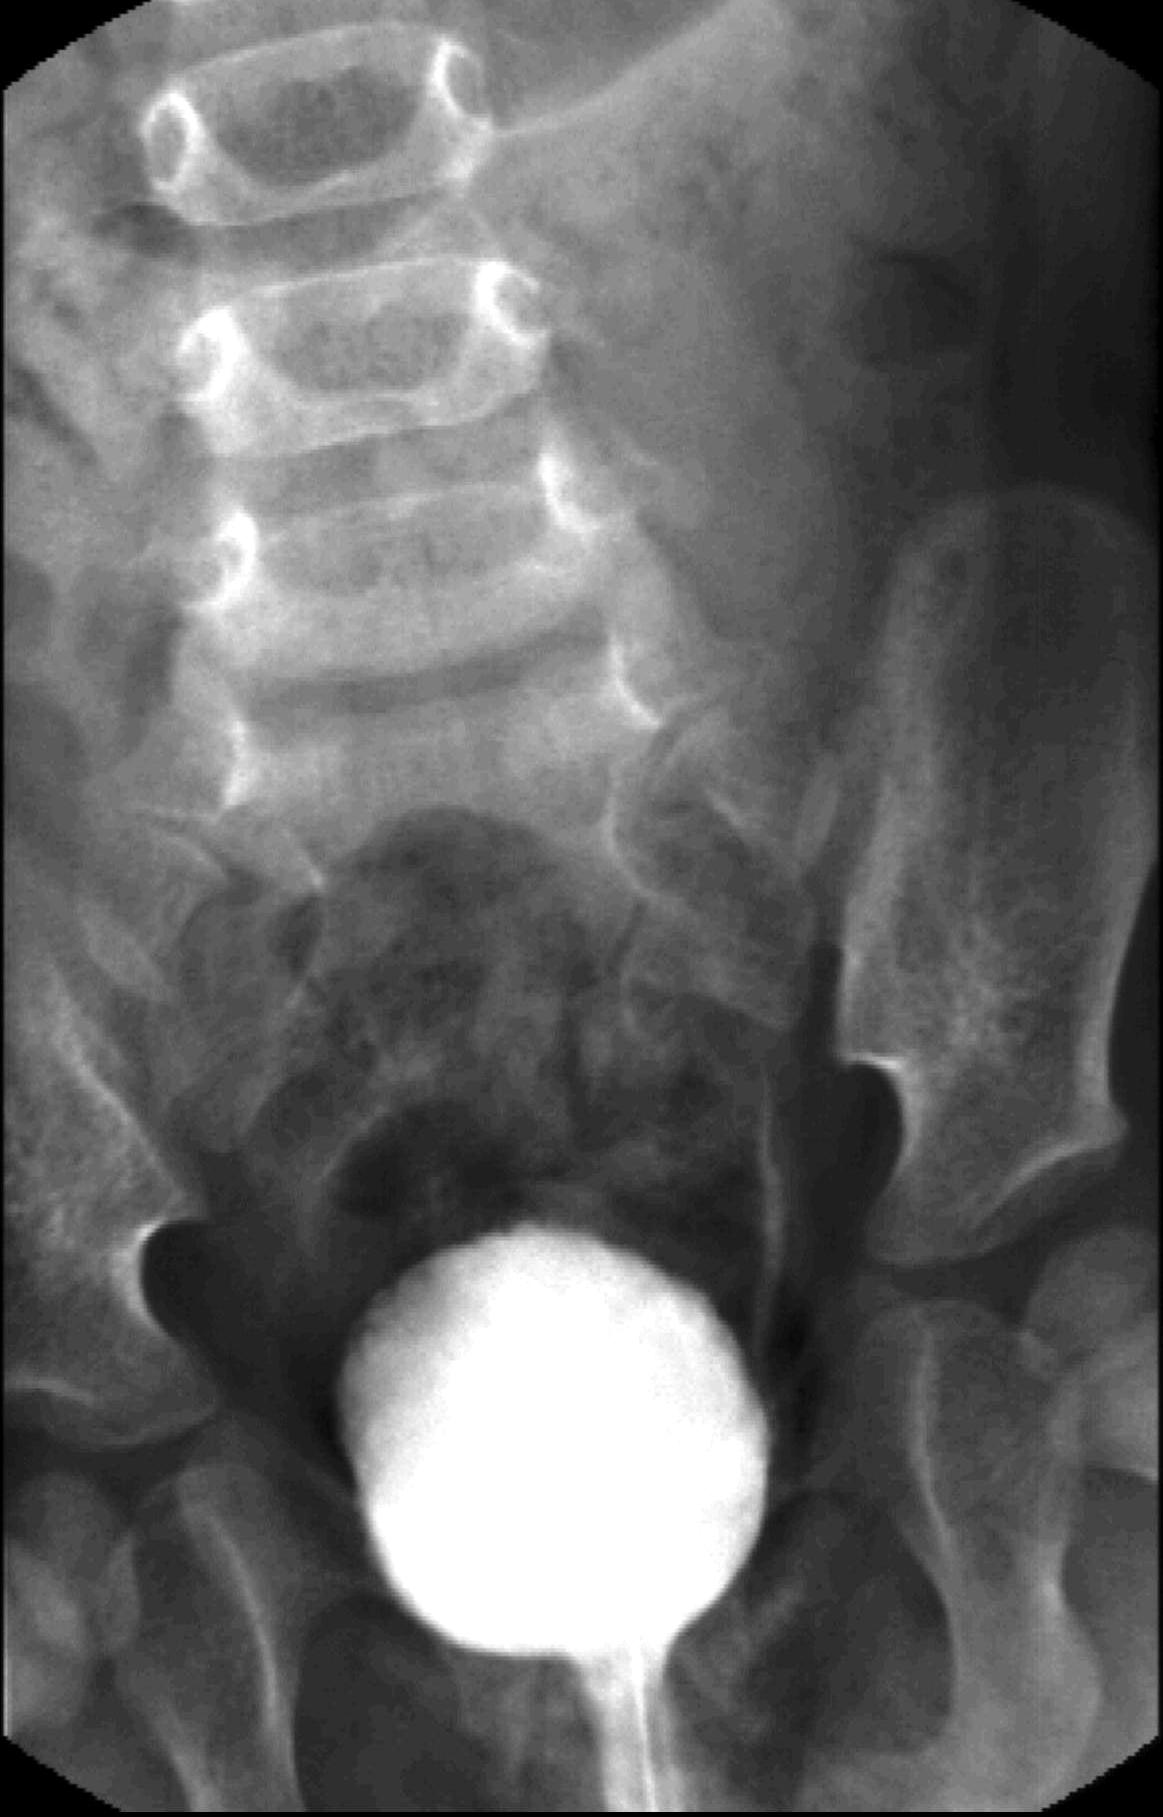

Distal urethral valve (subvesical obstruction). It is the most severe form of obstructive uropathy. In newborn boys the valve dysfunction can lead to bilateral obstruction with hydronephrosis and hydroureter. Urination can only occur intermittently. The bladder wall is thickened, trabecular and reflux is frequent. The proximal urethra is distended as well.

23. Miction cystourethrography. A small diverticula is seen on the right side, the proximal urethra is dilated, beneath is a filling defect. Subvesical obstruction, dorsal urethral valve.